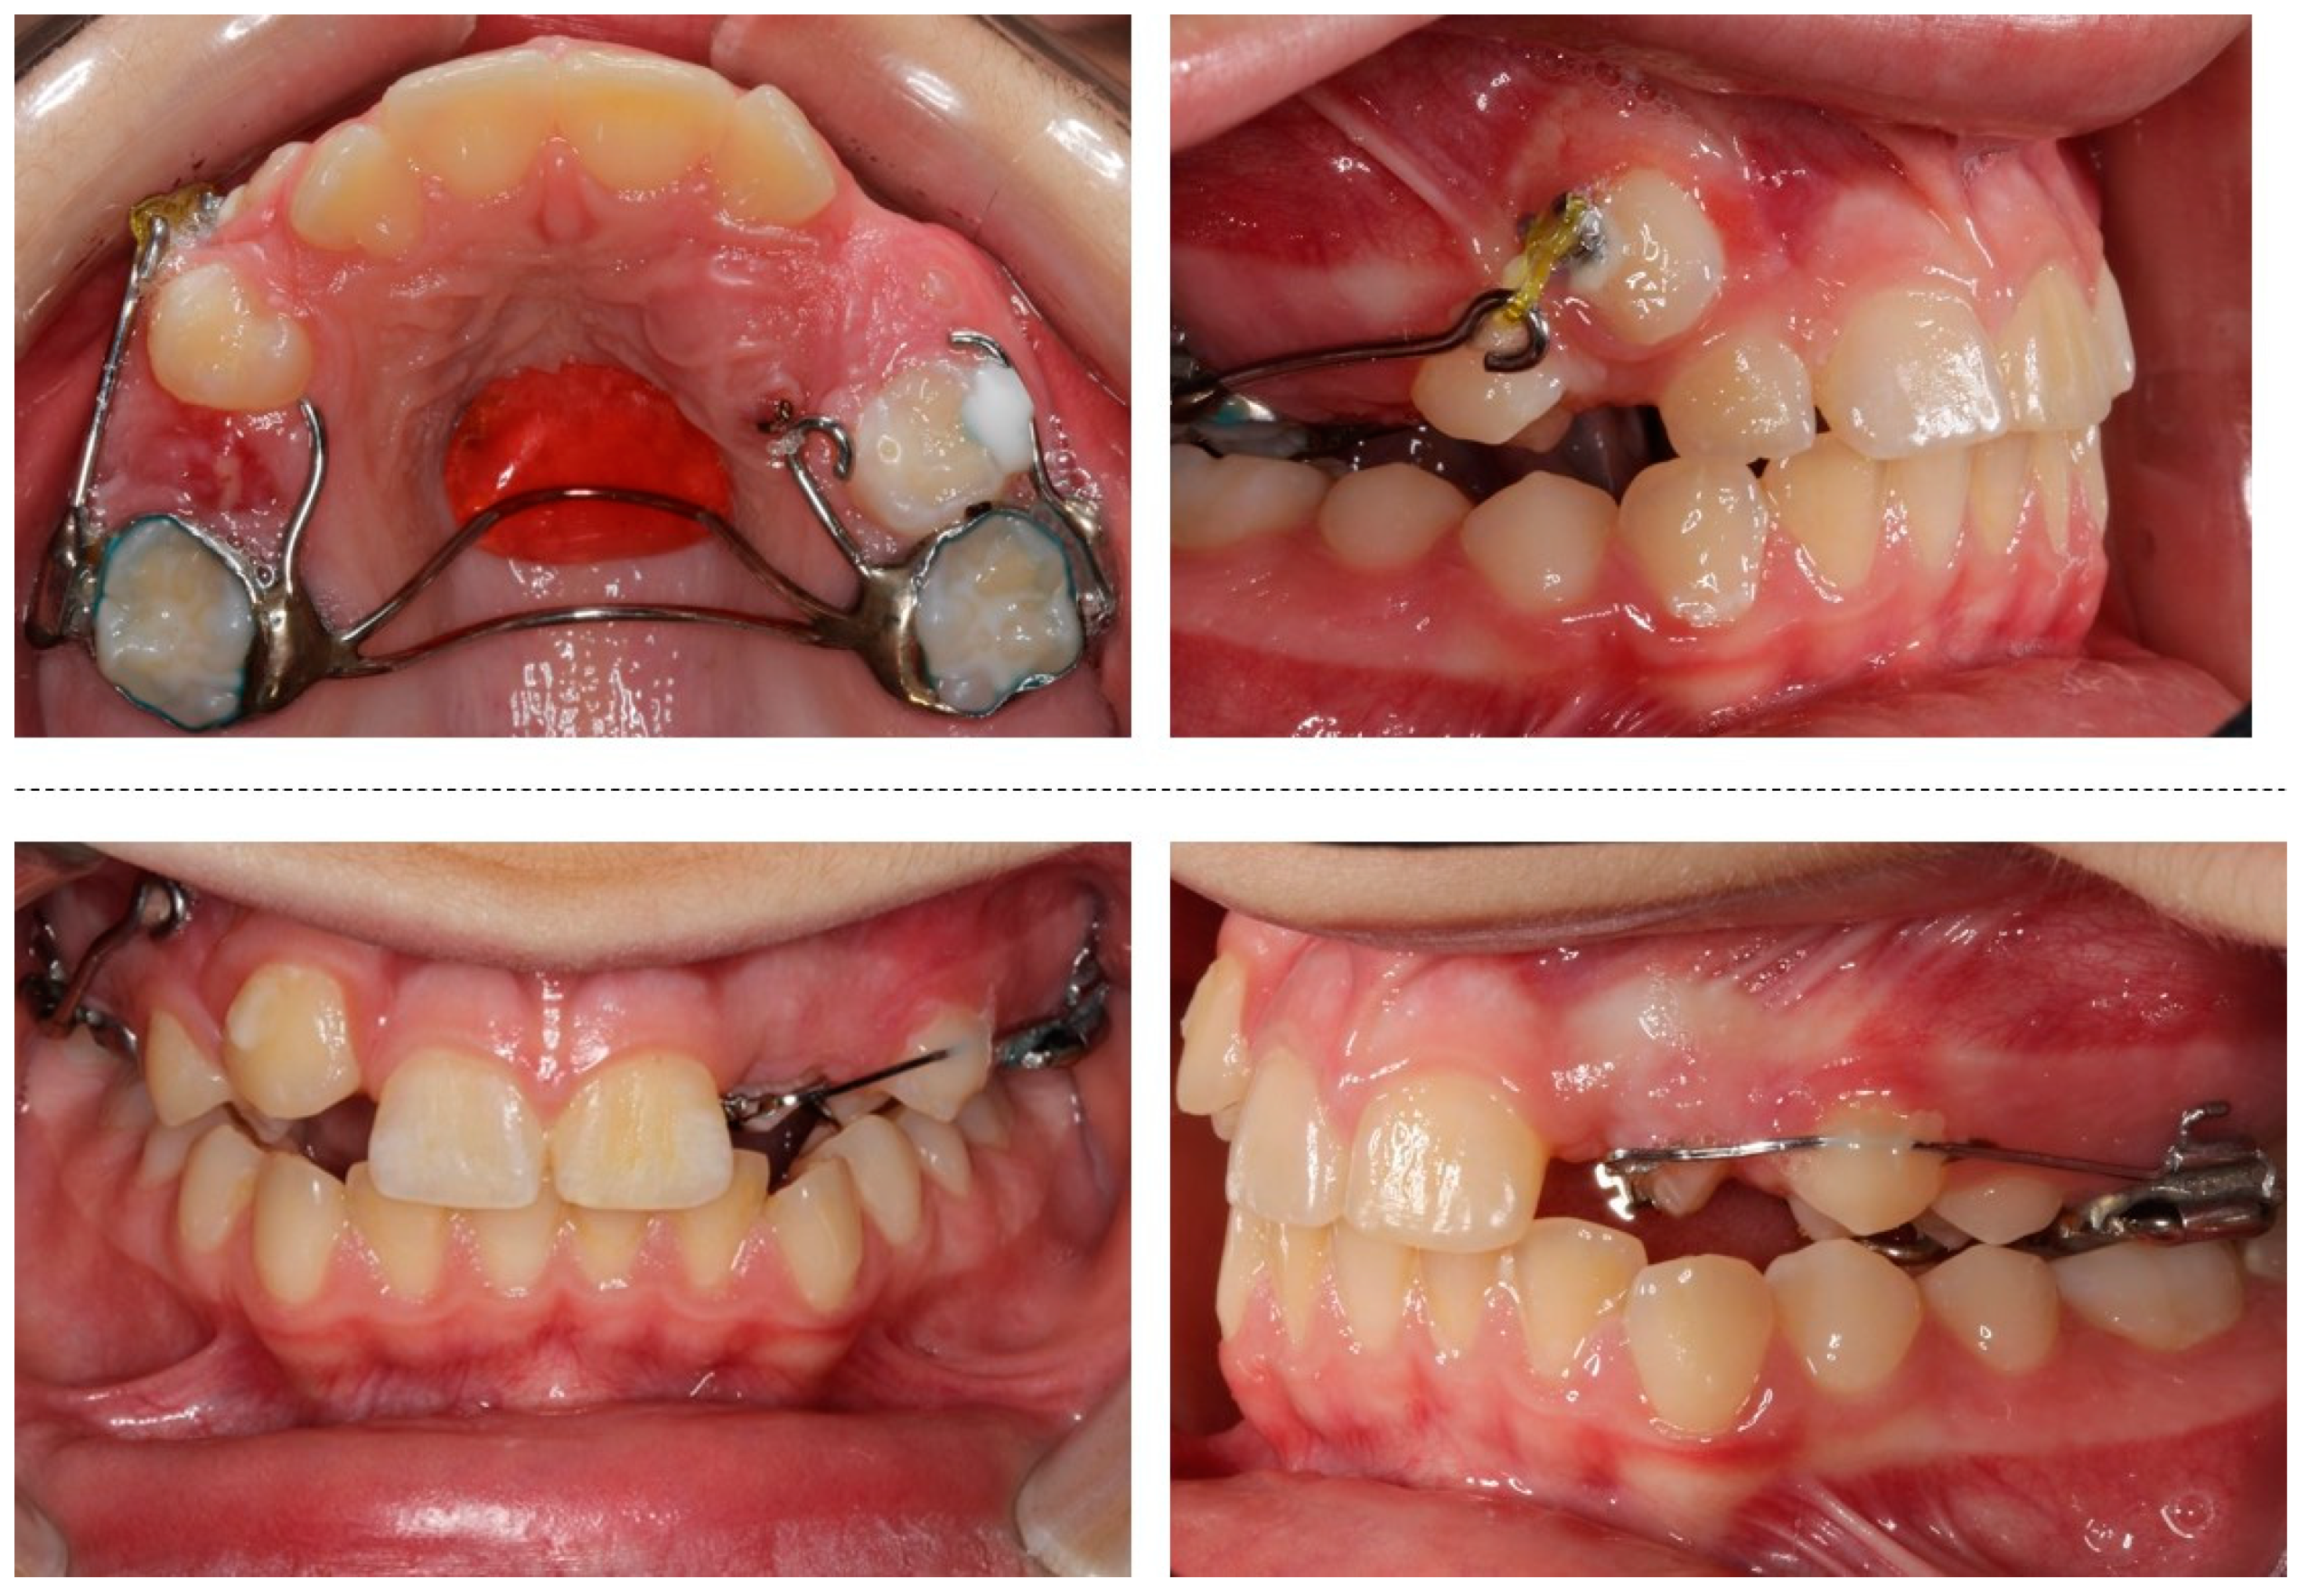

The orthodontic treatment was initiated with the canine exposure (Figure 5) and traction with light forces using a custom-made trans-palatal arch for anchorage purposes (Figure 6 and Figure 7). An open surgical technique (apically positioned flap) was used to expose the labially positioned right canine and a closed technique for the left, which was positioned palatally. Sectional mechanics were applied during treatment until the eruption of all permanent teeth (Figure 8). The upper lateral incisors were extracted after the successful eruption of the impacted canines and for aesthetic reasons. Subsequently, comprehensive orthodontic treatment was performed using fixed 0.018-inch-slot edgewise appliances. A lower lingual arch was placed to preserve the leeway space thus helping with the lower crowing. The progression of the archwire sequence was from 0.014-inch nickel-titanium to 0.016-inch Australian archwires. Class III light elastic forces were used bilaterally to help with space closure on the upper arch.

The custom-made trans-palatal arch used for the traction of the impacted canines.

Figure 7.

Progress photographs of the custom-made trans-palatal arch used for the traction of the impacted canines.

Figure 8.

Sectional mechanics used for the traction of the impacted canines.

2.4. Treatment Results

After a total treatment of 3 years and 2 months, a group function occlusion was achieved, with positive overjet and overbite. No interferences in the non-working side were present with lateral movements. The canines underwent composite resin restorations to resemble the lateral incisors (Figure 9).

Figure 9.

Post-treatment extra- and intra-oral photographs.